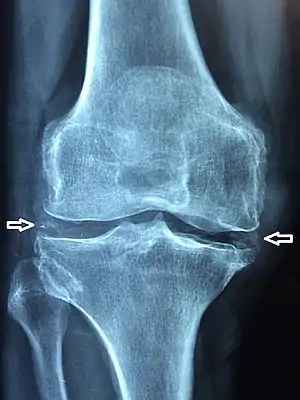

Chondrocalcinosis or cartilage calcification is calcification (accumulation of calcium salts) in hyaline cartilage and/or fibrocartilage.[1] It can be seen on radiography.

Chondrocalcinosis can be visualized on projectional radiography, CT scan, MRI, US, and nuclear medicine.[1] CT scans and MRIs show calcific masses (usually within the ligamentum flavum or joint capsule), however radiography is more successful.[1] At ultrasound, chondrocalcinosis may be depicted as echogenic foci with no acoustic shadow within the hyaline cartilage.[8] As with most conditions, chondrocalcinosis can present with similarity to other diseases such as ankylosing spondylitis and gout.[1]